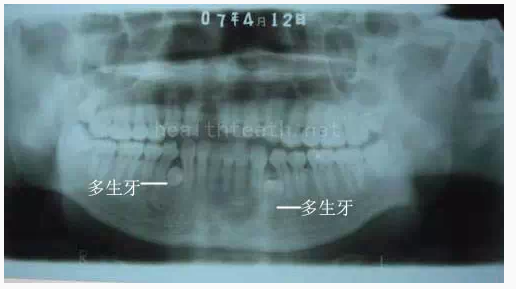

3、多生牙

病例3,同時多生兩顆牙齒